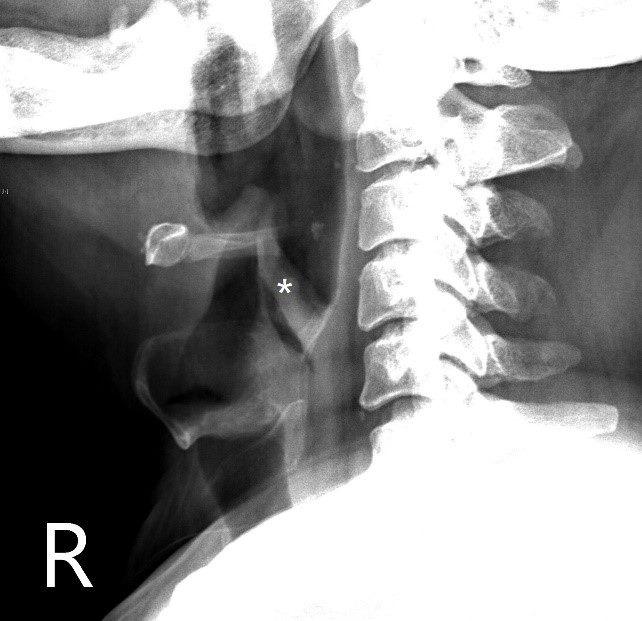

莊先生53歲,因吞嚥困難、疼痛、流口水等症狀,緊急至急診就醫,經頸部側面X光及喉內視鏡檢查,發現一大型異物堵塞於食道入口。透過胃鏡將異物取出,並給予消腫藥物,症狀得以緩解。